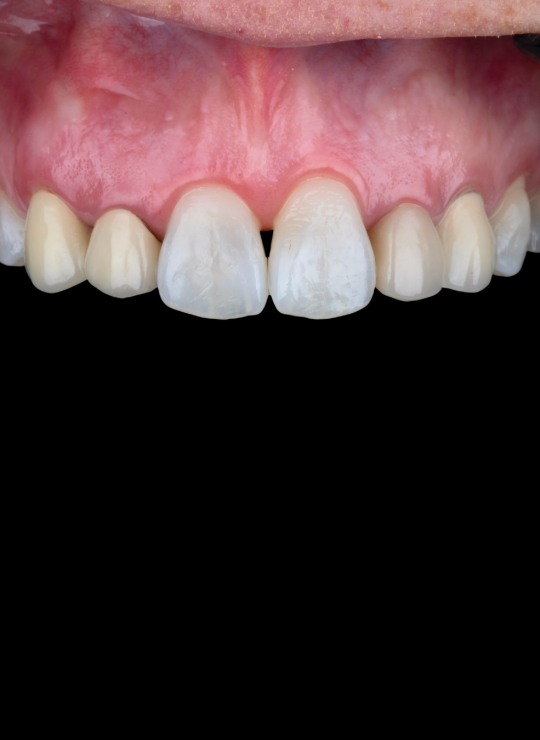

Introduction & biologic principles: supracrestal tissue attachment and biologic width

Review of literature: crown lengthening, altered passive eruption, gummy smiles, zenith positions

Diagnosis and treatment planning for anterior cases: smile line, lip dynamics, gingival asymmetry, periodontal phenotype

Case demonstrations: gummy smile correction, uneven gingival margins, anterior restorative integration (veneers, crowns)